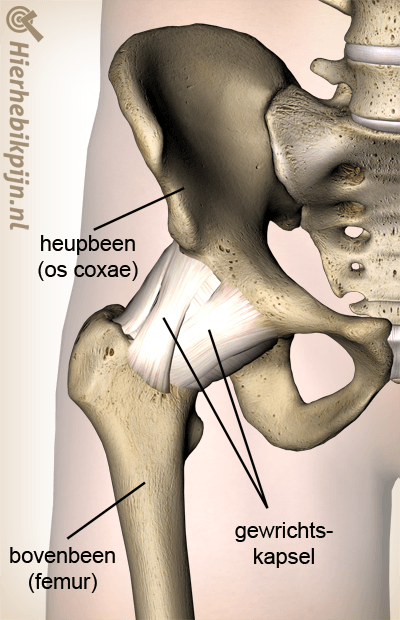

Heup